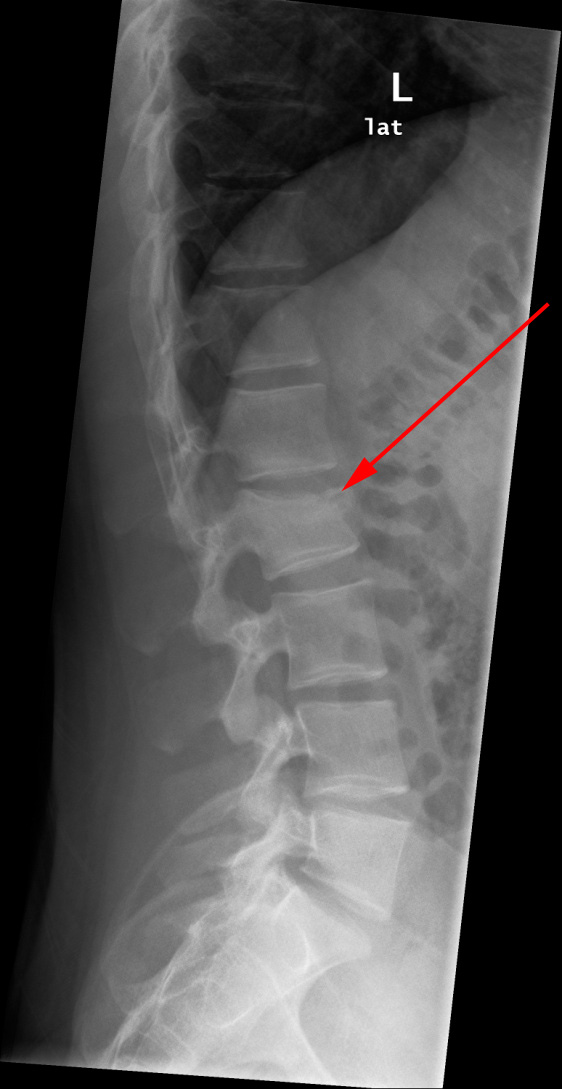

Columna lumbalis, kompressionsfraktur, røntgen

Røntgenundersøgelse af ryggen viser frisk kompressionsfraktur i corpus L2 (rød pil).